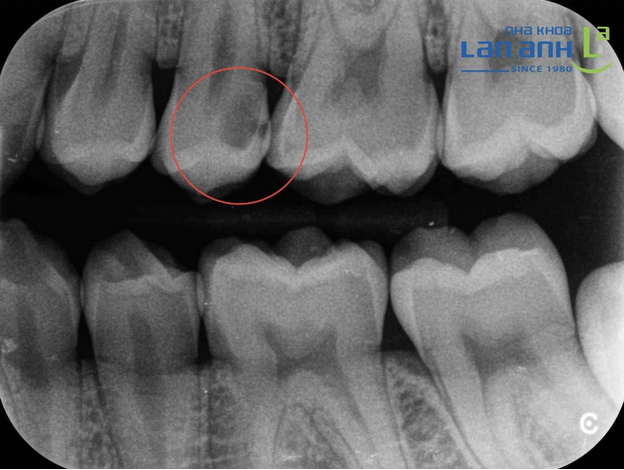

Is Tooth Decay Easily Detected With The Naked Eye?

Many people think that detecting tooth decay is easy, just ask the doctor to look at it, but it is not!